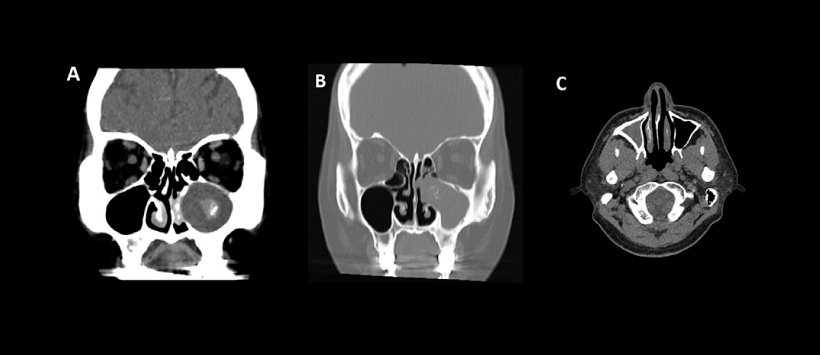

Figura A, corte coronal de TC que muestra una imagen hiperdensa (punto de calcificación), asociado a contenido en el seno maxilar izquierdo.

Figura B, corte coronal de TC que muestra una imagen hiperdensa (puntos de calcificación), asociado a contenido en el seno maxilar izquierdo con erosión de la pared lateral de la fosa nasal izquierda.

Figura C, corte axial de TC que muestra opacificación del seno maxilar derecho con esclerosis de las paredes anterior y posterior.